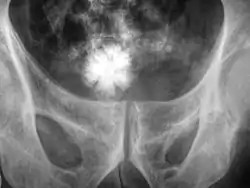

![]() ويمكن مُلاحظة حصاة على شكل نجمة في المثانة البولية بالأشعة قريبة من الحوض. ويمكن مُلاحظة حصاة على شكل نجمة في المثانة البولية بالأشعة قريبة من الحوض. | |